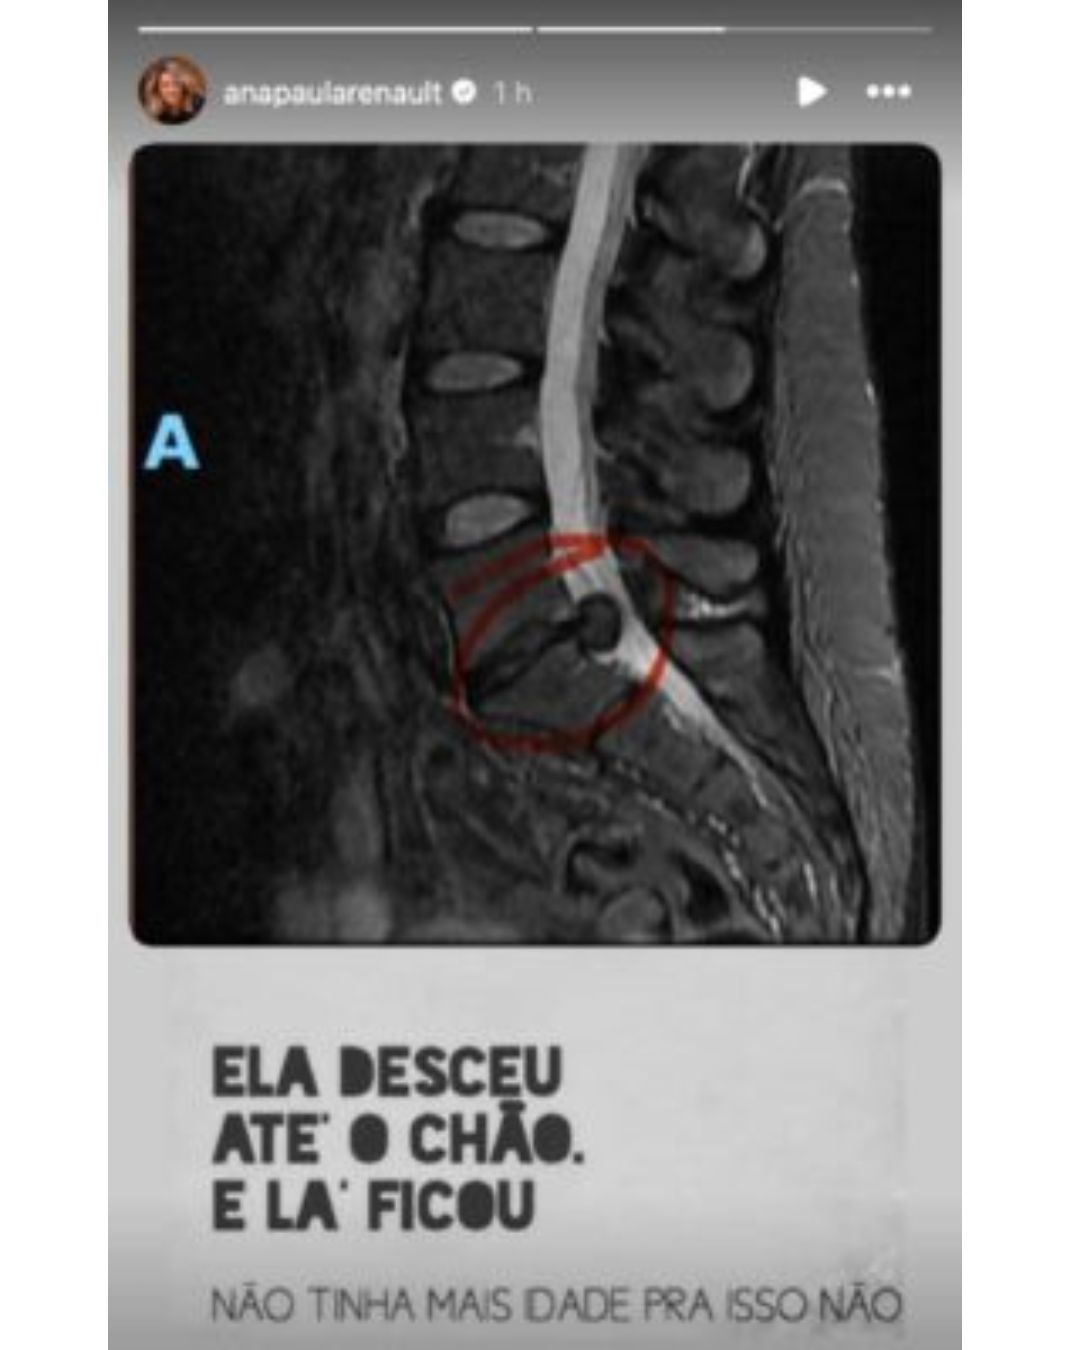

Uma imagem do exame foi mostrada por ela para comprovar a gravidade da hérnia. “Eles fizeram uma ressonância magnética e ficaram apavorados com o tamanho da hérnia. Por isso que já está comprimindo tudo e estava com essa dor excruciante.”

Foto do exame compartilhado por Ana Paula Renault - Foto: Reprodução/ Instagram